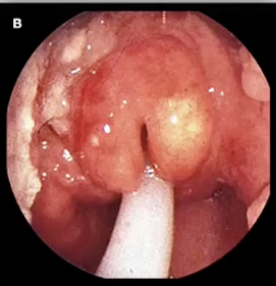

Helicobacter Pylori- Gram (-) rods, curved, urease positive, CAG pathogenicity island produced CagA protein and sheathed flagella

Helicobacter Pylori - Gram (-) rods, curved, urease positive, CAG pathogenicity island produced CagA protein and sheathed flagella